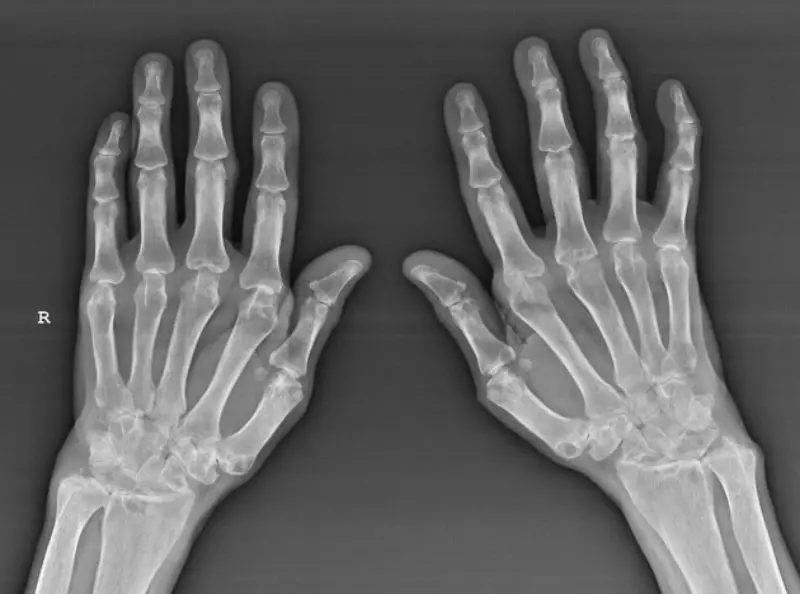

Chẩn đoán chính xác viêm khớp nhiễm khuẩn đóng vai trò then chốt trong việc lựa chọn phương pháp điều trị phù hợp. Các phương pháp chẩn đoán hiện nay bao gồm các xét nghiệm lâm sàng, xét nghiệm máu, dịch khớp, hình ảnh y học như X-quang, siêu âm hoặc MRI để phát hiện tình trạng viêm, tổn thương cơ học hay sự xuất hiện của vi sinh vật.

Trong nhiều trường hợp, bác sĩ còn chỉ định làm xét nghiệm dịch khớp để tìm vi khuẩn, vi sinh vật gây bệnh sinh mủ hoặc các chất viêm chỉ điểm rõ ràng. Đặc biệt, các slide hướng dẫn hoặc tài liệu như viêm khớp nhiễm khuẩn slideshare có thể giúp người bệnh dễ dàng hiểu rõ hơn về quy trình chẩn đoán và cách phân biệt các dạng viêm khớp khác nhau. Đánh giá kỹ lưỡng từ các phương pháp này giúp xác định chính xác bệnh, từ đó đưa ra phác đồ điều trị thích hợp.